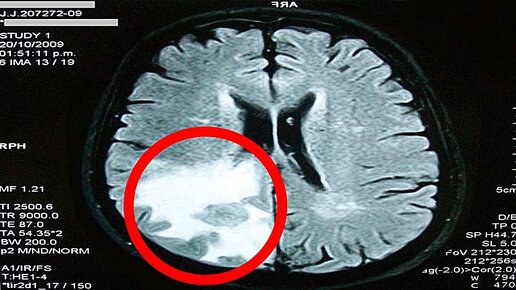

Ученые Утверждают, Что Забывчивость - ЭТО Признак Того, Что с Мозгом Происходит